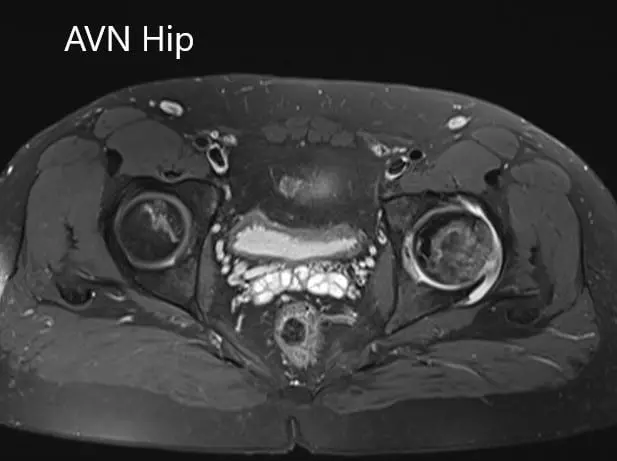

Imaging studies obtained in the form of an X-Ray suggested sclerosis of the left head of the femur. There were marked acetabulum changes. An MRI was further obtained suggesting avascular necrosis of the superior lateral head of the femur with changes in the acetabulum. There was marked hypointense areas on both T1WI and T2WIs.

Axial sections of the T2WI

Axial sections of the T1WI and T2WI of MRI.